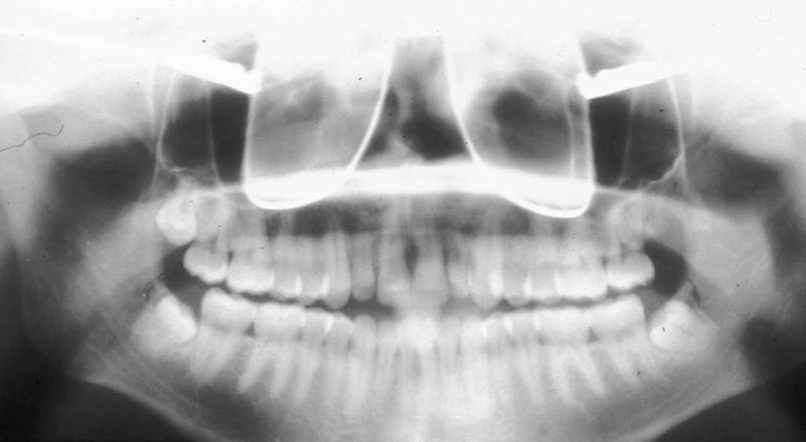

What is wrong with this image?

Inferior turbinates and meati spread across maxillary sinuses (too far back)

(also ghost image of earrings?-haley)